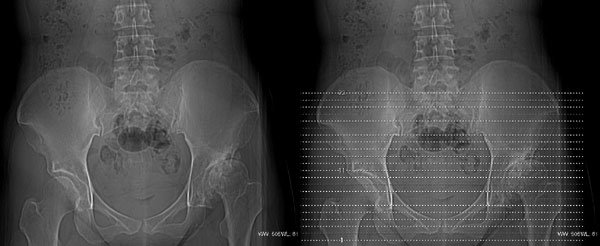

以下是引用jiajie在2006-7-14 17:19:00的发言:[br]ct所见:双侧髋关节不对称,左侧关节间隙变窄,关节面毛糙。左侧股骨头变形、无明显变小,前上缘与髋臼融合,融合处骨质明显增生硬化,并见数个小囊变影。股骨头下端与股骨颈交界部见囊样变,邻近肌肉内见囊样密度减低区,ct值24hu。右侧髋关节形态未见异常。[br][br]ct诊断:左侧髋关节结核可能,请结合临床资料进一步分析。

以下是引用lihuuuu在2006-12-5 10:14:00的发言:[br]定位像示:左侧髋臼变浅,倾斜度加大,髋臼外上缘呈波浪状不规则,骨质增生硬化,髋关节上缘间隙明显变窄,股骨头向外上轻度移位。轴位像示:左侧股骨头变形,前上缘与髋臼融合,融合处骨质明显增生硬化,并见数个小囊变影。股骨头下端与股骨颈交界部见囊样变,邻近肌肉内见密度减低区,ct值24hu,内缘见弧形高密度钙化影。右侧髋关节形态未见异常。[br]ct诊断:左侧髋臼发育不良[br] 左侧股骨头缺血性坏死[br] 左侧肌肉内低密度影伴有高密度钙化-考虑早期骨化性肌炎[br] [br]“我认为在描述上已经写了肌肉部分,印象诊断里应该写主见”[br]